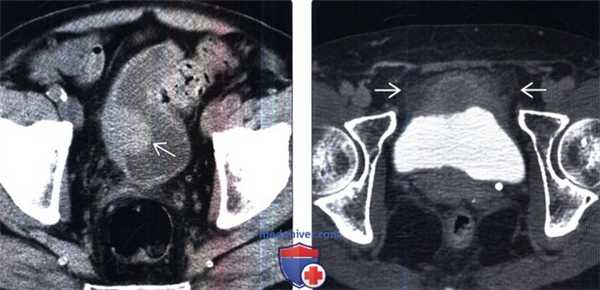

(Слева) КТ без контрастирования, аксиальный срез: у пациента с гематурией в анамнезе определяется полипоидное образование мягкотканной плотности вдоль боковой стенки мочевого пузыря. Была выполнена трансуретральная резекция опухоли мочевого пузыря (ТУР). При патоморфологическом исследовании был выявлен плоскоклеточный рак.

(Справа) КТ с контрастированием: заметное неравномнерное утолщение передней стенки мочевого пузыря. Обратите внимание на уплотнение околопузырной клетчатки, что предполагает прорастание опухоли через серозную оболочку (стадия Т3). Была выполнена радикальная цистэктомия: при патоморфологическом исследовании была выявлена стадия T3N1.